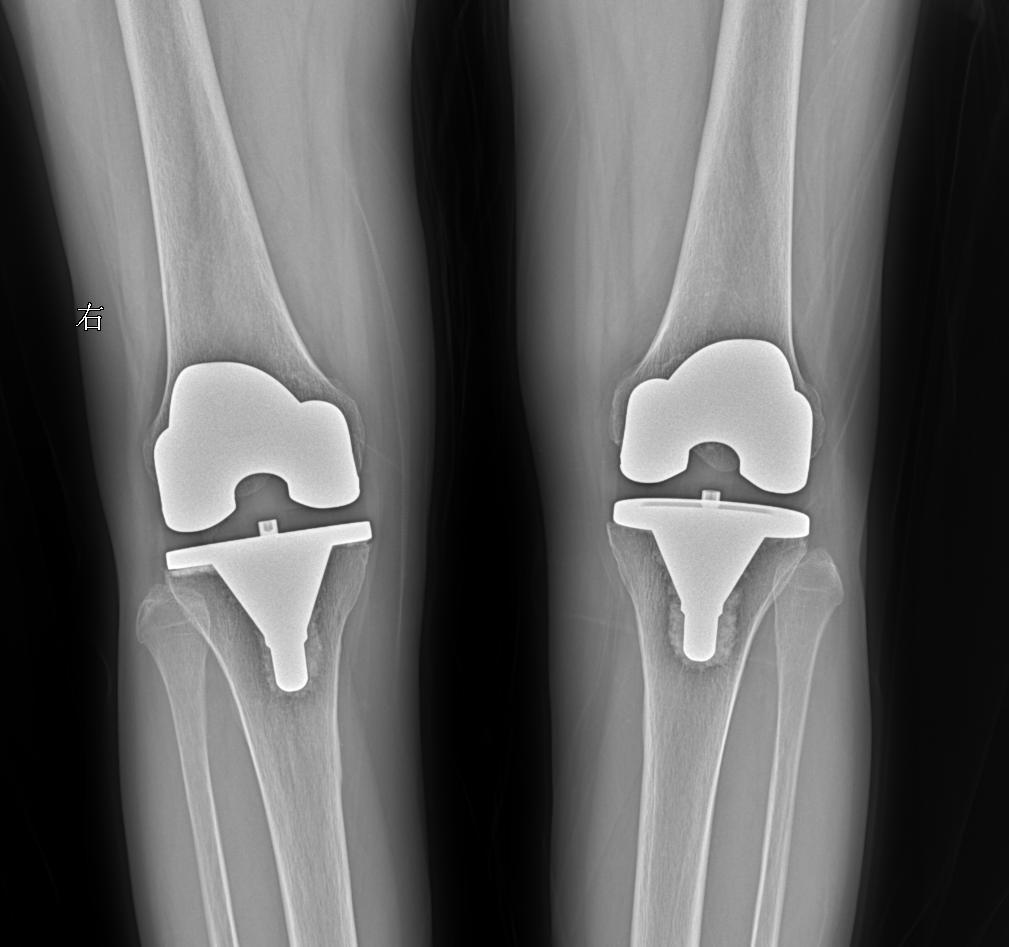

患者女 74岁行走时膝关节疼痛就诊

2025-02-28 16:07